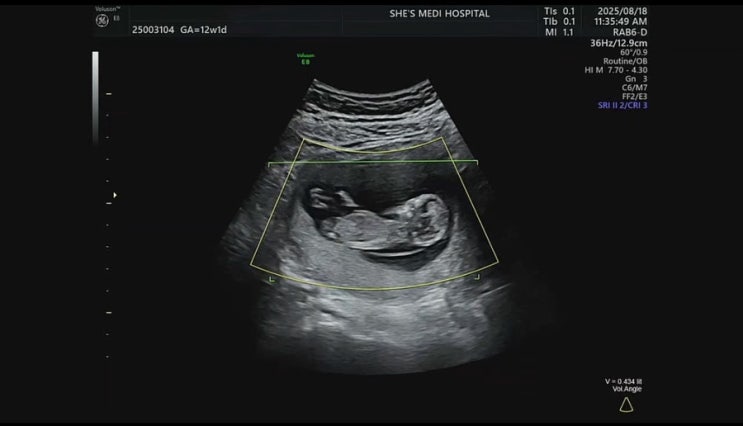

임신 기록 ep.01 | 우리에게도 새 생명이..♥ (0주~13주차 기록)

뚜둥...! 배테기로 자연 임신 시도에 도전 했던 6월... 25년 3월 부터 계속 시도해 왔으나 생각보다 쉽지 ...